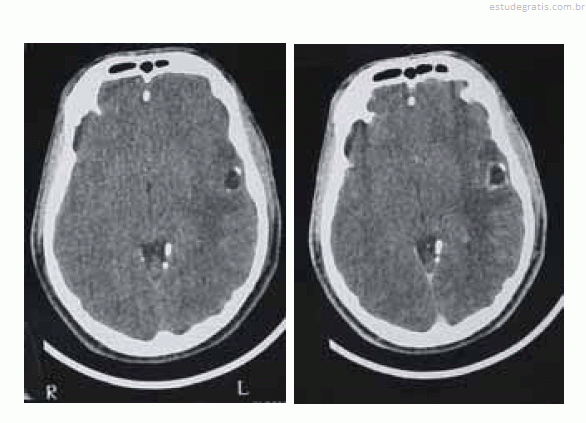

Uma paciente de 35 anos de idade foi levada ao prontosocorro após uma convulsão. Ao exame de admissão, encontravase confusa, sonolenta, porém reativa ao chamado. Apresentava sutil paresia braquiofacial direita. O esposo informou que, nos últimos cinco meses, a paciente começou a apresentar dificuldade para se comunicar, troca de palavras e dificuldade para nomeação. Há duas semanas, o quadro piorou e começou a ficar desligada e a apresentar abalos musculares no membro superior direito, de rápida duração, além de queixar-se de dor de cabeça. Foi realizada uma tomografia computadorizada (TC) de crânio, sem e com contraste, obtendo-se as imagens a seguir.

A imagem mostra um edema vasogênico, que tem como base a ruptura da barreira hematencefálica, levando a aumento da permeabilidade e passagem de líquidos do espaço intravascular para o extravascular, extracelular.